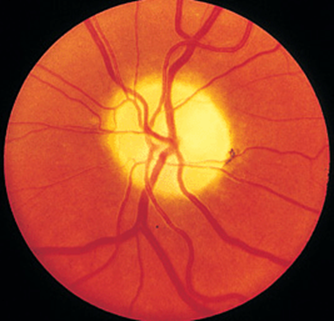

FIGURE 21-10

Retrobulbar optic neuritis is characterized by a normal fundus examination initially, hence the rubric “the doctor sees nothing, and the patient sees nothing.” Optic atrophy develops after severe or repeated attacks.